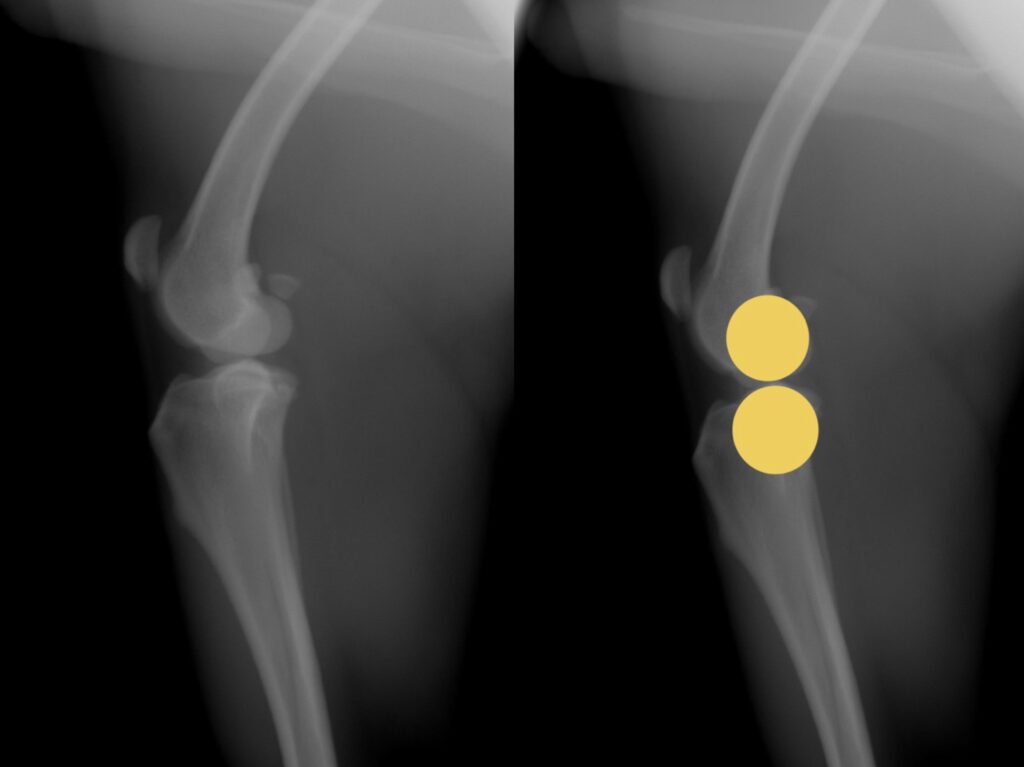

では、実際にはどうでしょうか。下のレントゲン写真は、同じ膝関節を、伸ばした状態と曲げた状態で観察したものです。

曲げ伸ばしで起こる関節の変化に図形を当てはめてみましょう。

上図のように。実際の膝関節は、円と円の構造というよりは、楕円と円の構造になっています。楕円の長軸と単軸の半径の違いによって、曲げ伸ばしの際の中心点間の距離が変わります。このため、前述した、『膝を曲げた状態に合わせて人工繊維を設置すると膝を伸ばした時には緩くなり、膝を伸ばした状態に合わせて設置すれば膝を曲げた時に人工繊維に過剰な力がかかってしまう』という問題が発生してしまい、これがECRの欠点となってしまっていました。